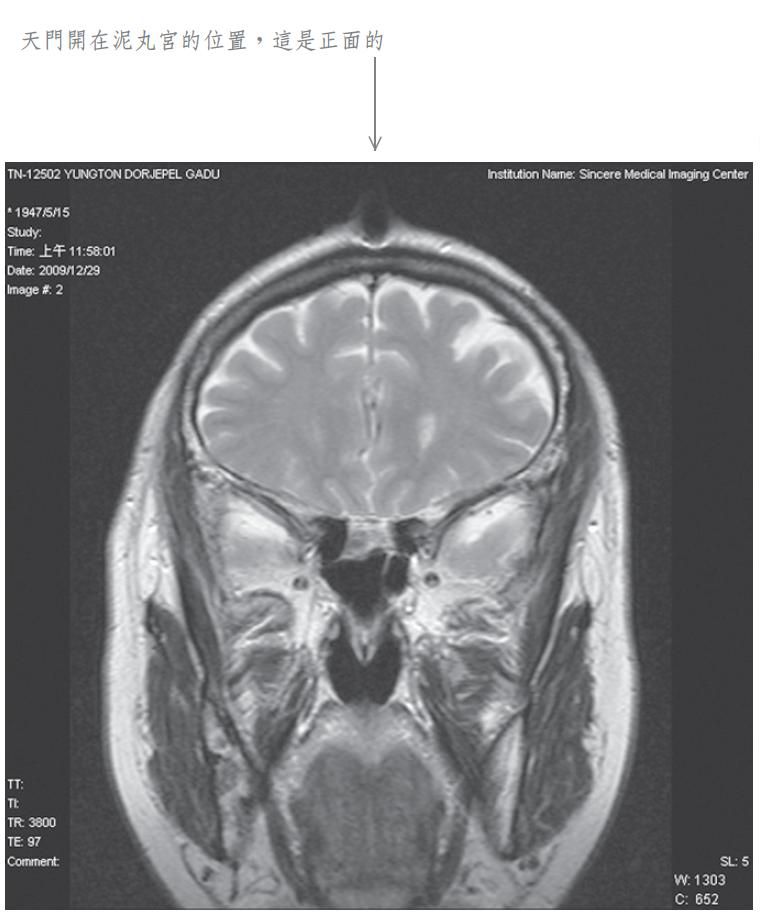

當我將此種修法中發生之覺受稟報佛陀師父時,佛陀師父又為我傳了秘密口訣。經過一段時日,佛陀師父在公開開示的法音帶中,才提到我曾經修法達到化身境的初級,即是素化身的意思。為了讓眾生明瞭佛法的偉大,事隔多年之後,我特別於二零零九年十二月廿九日,到中心綜合醫院安排磁振造影(MRI)頭部的攝影檢查,結果發現泥丸宮的部位出現一個1.5公分寬深的開口,同時拍下了有一股神識出氣衝出頭部的實況。負責檢查的醫生非常驚訝稱奇,但無法解釋其原因,因而將它歸因於非人之所為。我其實非常清楚,我的神識化身本來就是從這裡出入的,以下是在醫院MRI檢查的掃瞄片。